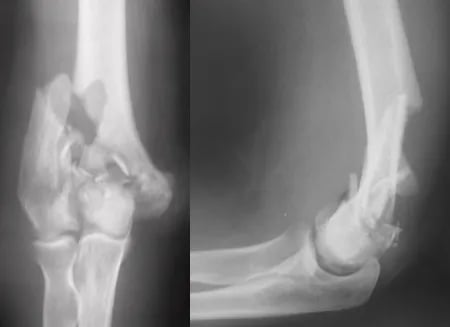

Fratura Distal do Úmero

O úmero, o osso do braço, articula-se com a ulna e o rádio no cotovelo. As fraturas da porção distal do úmero costumam ocorrer após queda ao solo. Esta é a fratura mais grave dentre as que podem acometer o cotovelo.